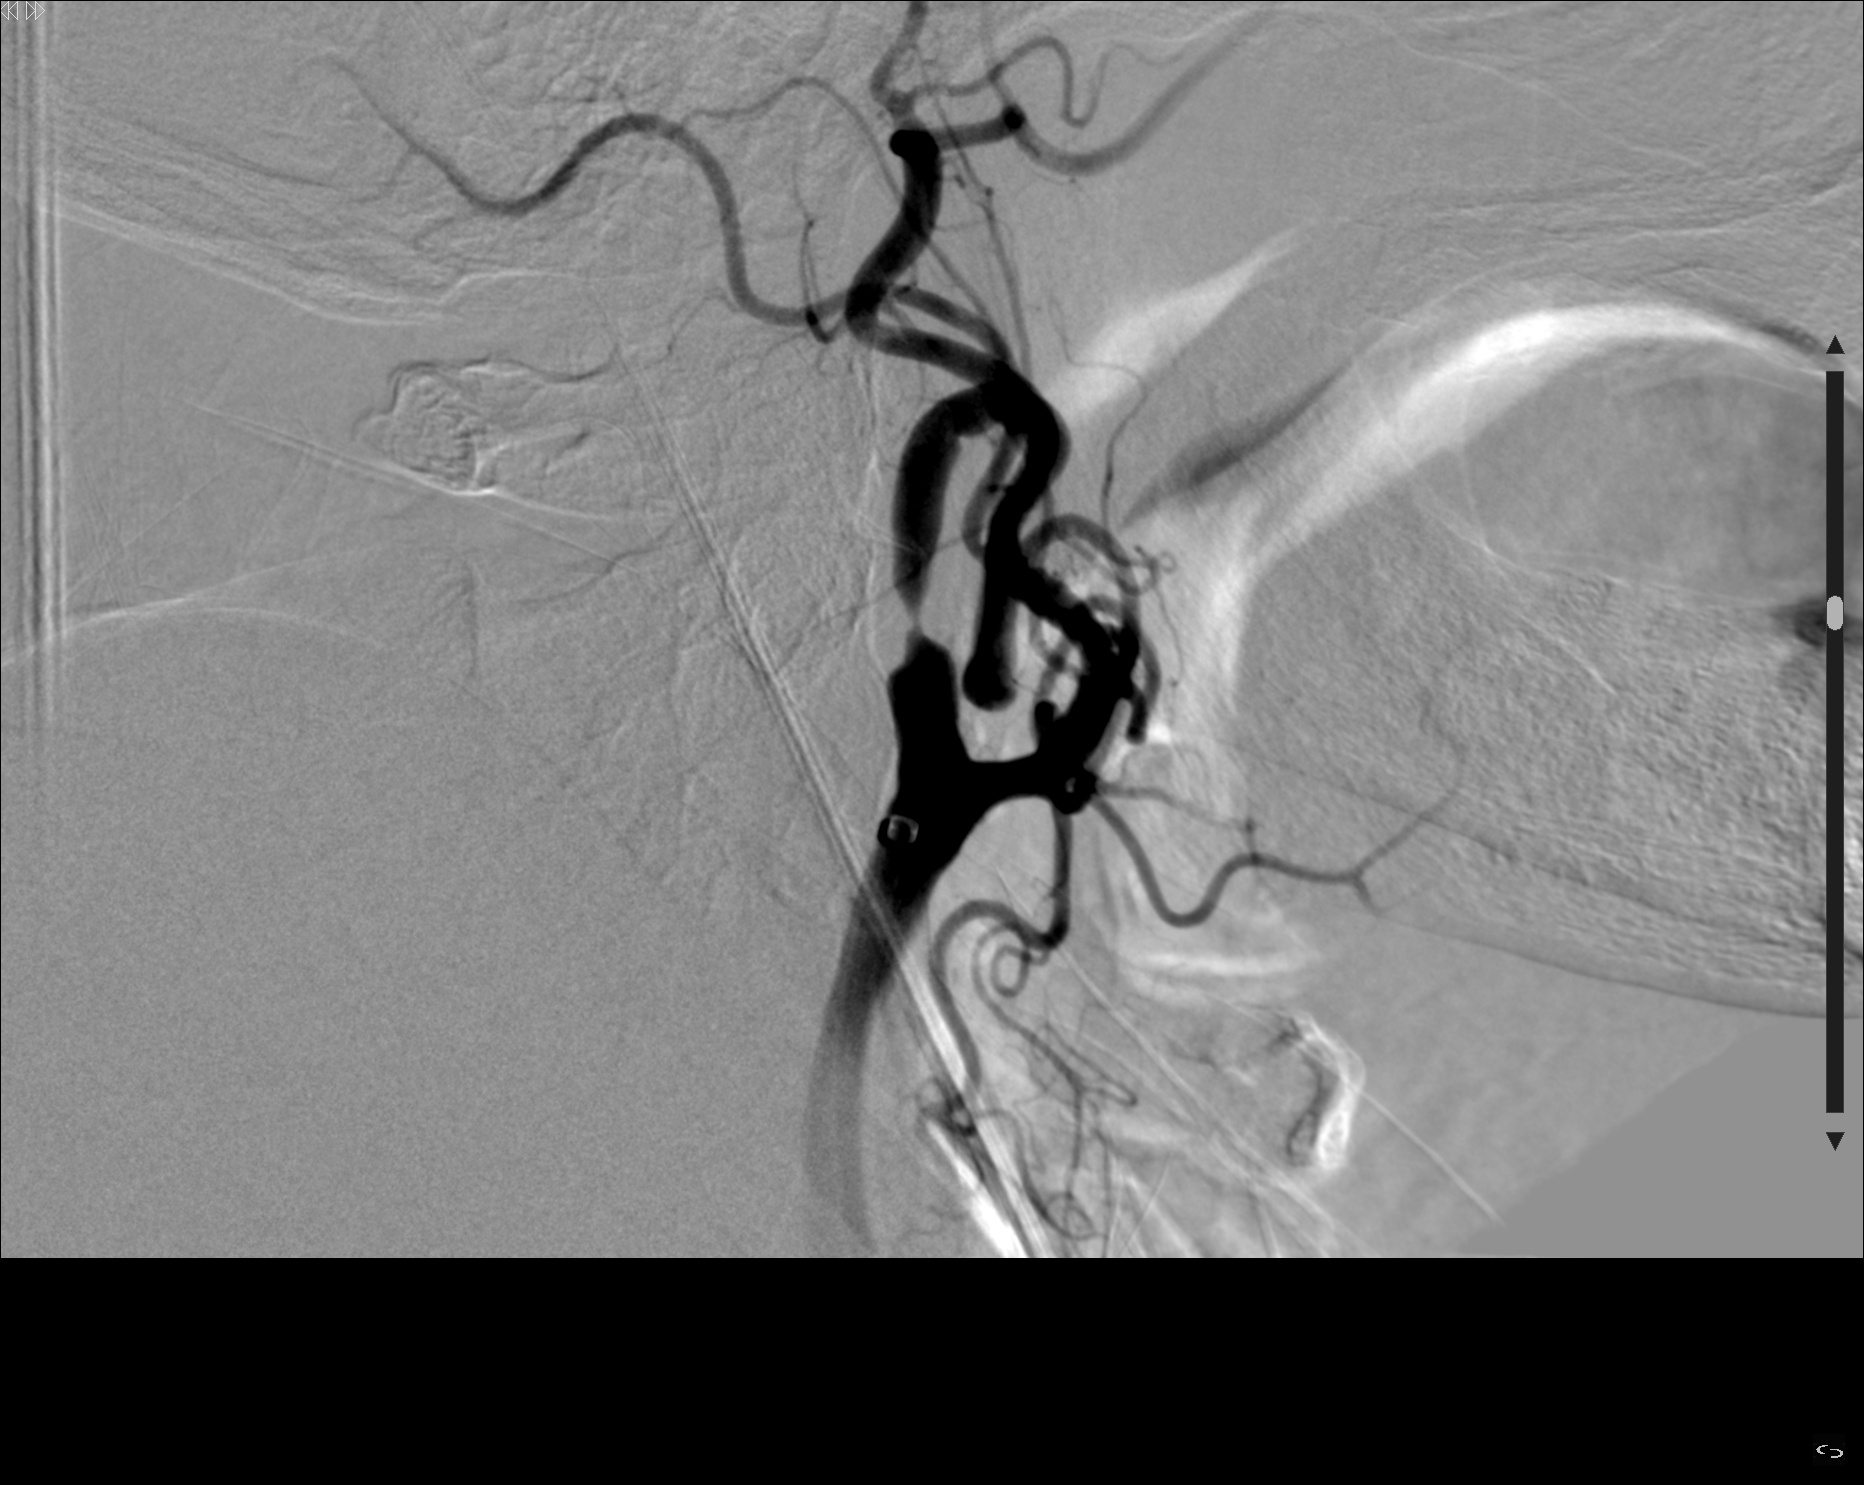

Se realiza punción femoral derecha. Se realiza cateterización selectiva de la arteria carótida común izquierda derecha y la primera serie angiográfica pone de manifiesto una estenosis mayor del 80% secundario a placa irregular ulcerada en el origen de la ACID. Se atraviesa

estenosis y se realiza angioplastia con balón. Se avanza introductor largo hasta ACID y se realiza serie sectiva observando una oclusión a nivel del segmento carotida terminal en T. Se procede al microcateterismo selectivo de arteria ocluida logrando una adecuada posición para realizar trombectomía, realizando 1 pase. En la serie de comprobación final se confirma recanalización TICI 2b, quedando oclusión distal en ACA (A3). Se realiza nueva serie en carótida común observando persistencia de estenosis con una placa ulcerada e

irregular en el origen de ACID. Se coloca un filtro en ACI distal de protección y se decide colocación de 2 Stent en ACI proximal de 9×40 y un segundo Stent 7×40, con resultado posterior satisfactorio, sin estenosis significativa residual